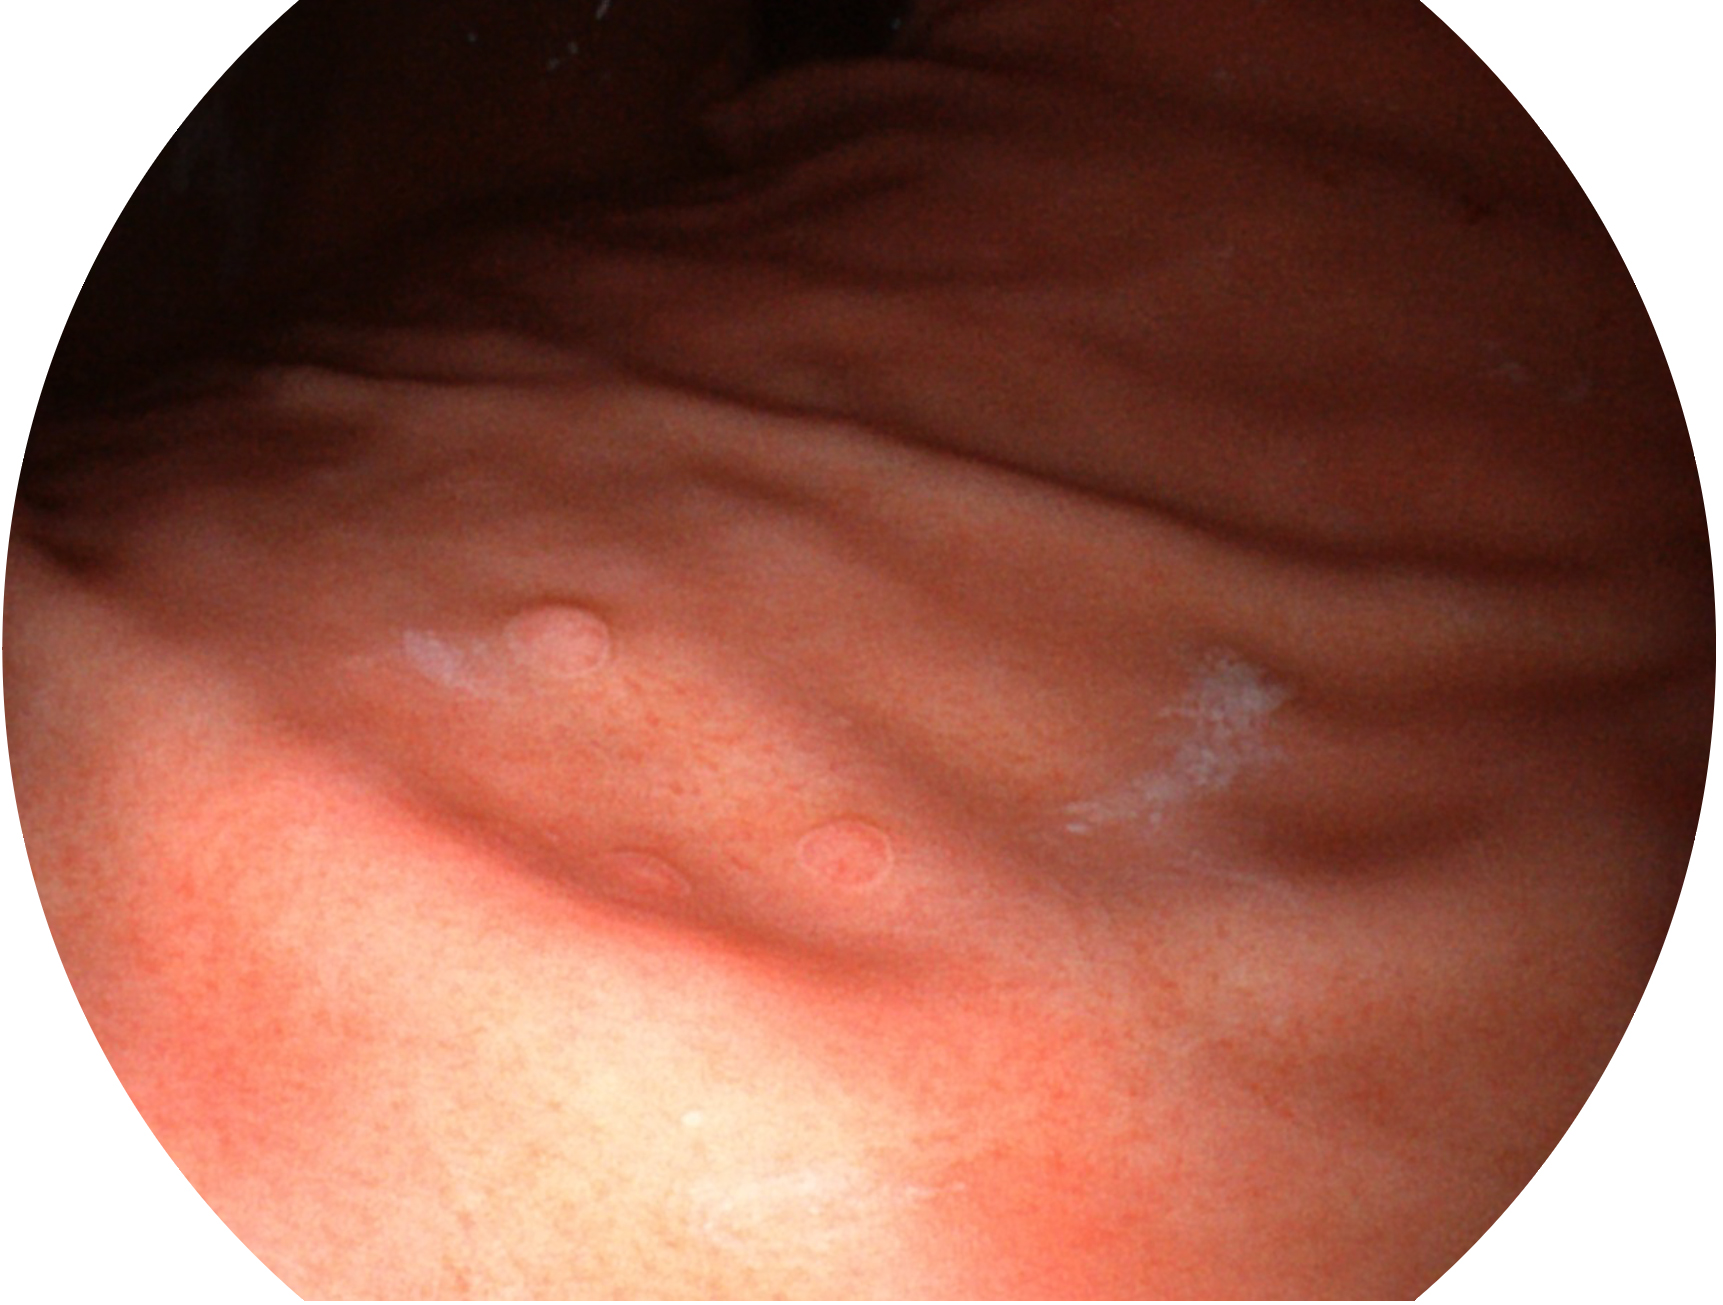

哈哈体育官网新开发的内镜染色技术,主要是基于多波长LED 光源的开发,VLS-55Q 四波长LED 光源是由四个不同颜色的LED光按照相应照明模式所规定的特定发光比例进行合束后形成,合束后形成的照明光的光谱由红光、绿光、蓝光及蓝紫光这四个不同的波段范围构成。具有更高光谱自由度,通过光谱比例的控制,实现了聚谱成像技术,英文全称为“Spectral Focused Imaging, SFI”,缩写为“SFI”和光电复合染色成像技术,英文全称为“Versatile Intelligent Staining Technology, VIST”,缩写为“VIST”。